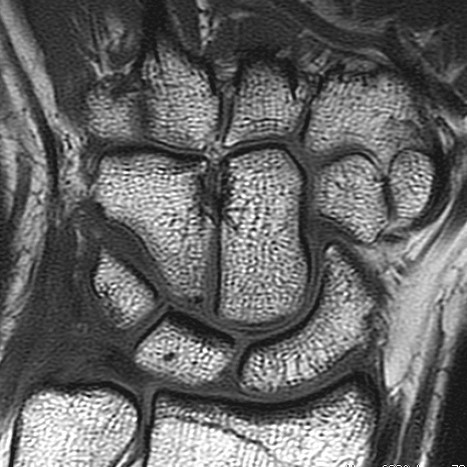

MSK CASES

www.mskradiology4u.co.uk

MSK Imaging Referral and Interpretation Course: Level 1

Course Content

Image Interpretation and the Radiological Report

Turn a working diagnosis into a more definitive diagnosis by understanding what the images show and the implications of the report. Understand how the images are formed and how to view.